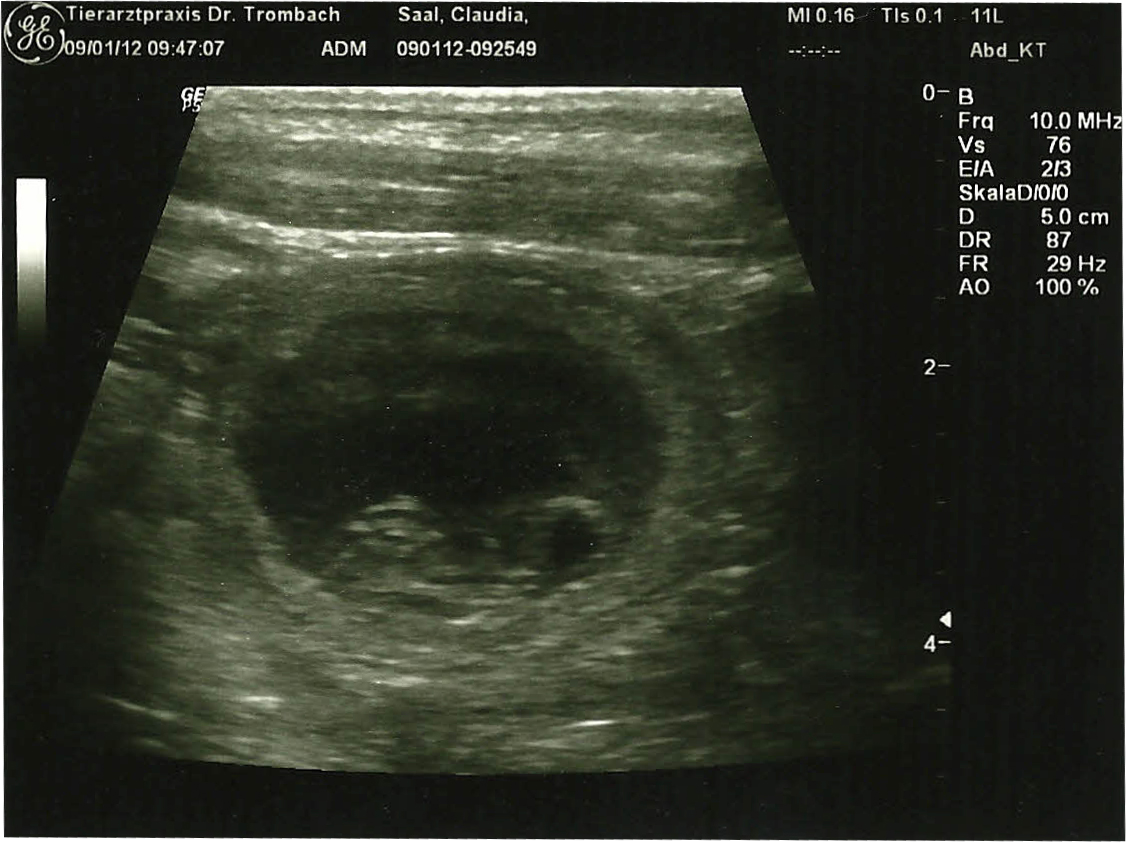

Wir waren heute beim Ultraschall: Carlotta hat aufgenommen!!!!!

Nach Aussage der Tierärztin wird's ein "ordentlicher" Wurf.

Hier einen ersten Eindruck eines bereits jetzt schon wohl erzogenen Welpen

:

Und den Herzschlag konnte man genau erkennen. Was für ein wunderschöner Moment. Wir freuen uns so!!